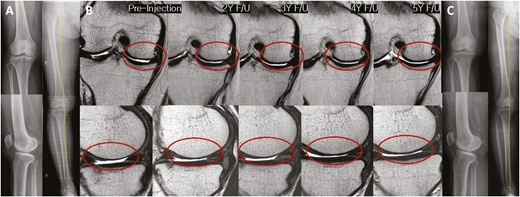

2022年5月14日,韓國江東慶熙大學醫(yī)院骨科在行業(yè)期刊《干細胞轉(zhuǎn)化醫(yī)學》上發(fā)表了一篇關(guān)于《關(guān)節(jié)內(nèi)注射間充質(zhì)干細胞治療膝骨關(guān)節(jié)炎的安全性和有效性:5年隨訪研究》的研究成果。【4】

招募了11名膝關(guān)節(jié)骨關(guān)節(jié)炎患者,并在單次關(guān)節(jié)內(nèi)注射自體高劑量 (1.0×108?) ADMSCs 的5年隨訪期間進行了系列評估。

- 注射后5年內(nèi)未見內(nèi)翻力線或KL等級分布明顯惡化(圖3)。

- 系列MRI檢查顯示,注射后3年內(nèi)MFC軟骨缺損面積呈減少趨勢,治療后5年內(nèi)未見明顯惡化(圖 4)。

- 內(nèi)側(cè)間室軟骨WORMS評分在注射后2至3年間均有明顯改善(2年,P=0.029;3年,P=0.031)(表3)。

- 治療后3年內(nèi),總體WORMS顯示出顯著改善,從73.4±27.8顯著下降至70.5±26.8(6個月;P= 0.020)、65.5±29.4(2年,P=0.016)和66.5±30.7(3年,P=0.041)(表3)。

- WORMS子評分還顯示,在注射后2至3年內(nèi)、注射后2年內(nèi)和注射后3年內(nèi),總軟骨狀態(tài)、骨髓水腫和滑膜炎均有顯著改善。

安全性評估:在隨訪的6個月至5年期間,關(guān)節(jié)內(nèi)注射ADMSCs后未報告任何治療相關(guān)不良反應。

綜上所述,VAS和總WOMAC評分在注射后6個月以及直到最新隨訪時均顯著改善。總WORMS在注射后3年內(nèi)顯著改善。

單次關(guān)節(jié)內(nèi)注射自體高劑量ADMSCs可在5年內(nèi)提供安全的臨床改善,且不會出現(xiàn)放射學加重。此外,骨關(guān)節(jié)炎膝關(guān)節(jié)的結(jié)構(gòu)變化在長達3年的時間內(nèi)顯示出顯著改善,這表明它可能是膝關(guān)節(jié)OA患者的疾病改良治療的一種可能選擇。